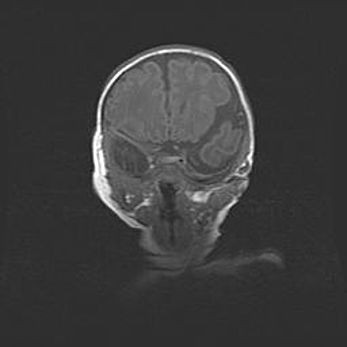

Неполная лизэнцефалия (пахигирия). Открытая гидроцефалия.

Возраст: 17 дней

Вес: 3110 г

Пол: мужской

Окружность головы: 33,5 см

Срок гестации: 35-36 недель

Лизэнцефалия—недоразвитие корковой пластинки и мозговых извилин в результате нарушения миграции нейронов коры. Поверхность мозговых полушарий гладкая. Микроскопически выявляется отсутствие нормальных слоев коры и скопление групп нейронов в подкорковом белом веществе.

Пахигирия—уменьшение числа вторичных извилин. В пораженном полушарии нервные клетки образуют толстый недифференцированный слой с неправильно расположенными нервными волокнами и группами гетеротопных клеток. Нервные клетки незрелые. Белое вещество истончено. При этом нередко аномально развит корково-спинномозговой путь.